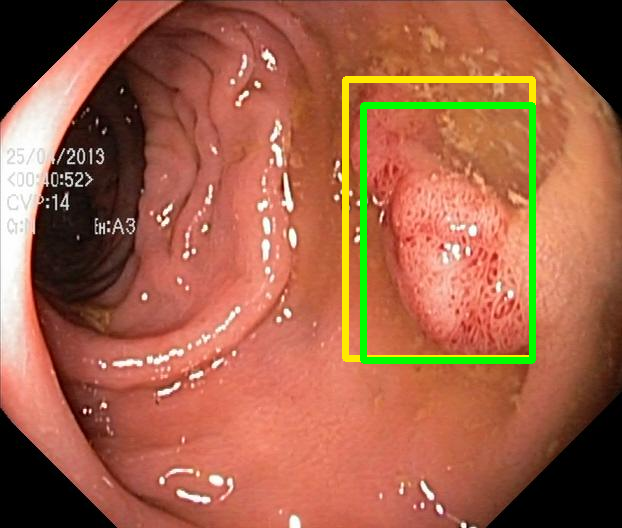

We evaluate the resulting object detection models using the test data, which is pre-processed in the same manner as the validation data, with AP@[.5:.95] (AP for conciseness), AP@.5 (AP5050{}_{50}start_FLOATSUBSCRIPT 50 end_FLOATSUBSCRIPT), and AP@.75 (AP7575{}_{75}start_FLOATSUBSCRIPT 75 end_FLOATSUBSCRIPT) computed for predicted bounded boxes with a confidence score \geq0.05. For all metrics, a higher value indicates better performance. The results are presented in Table VI, and some examples for predicted bounding boxes with a confidence score \geq0.5 are shown in Fig. 1.

RN-HK-MC RN-HK-BT RN-IN-MC RN-IN-BT RN-IN-SL RN-NA-NA Refer to caption Refer to caption Refer to caption Refer to caption Refer to caption Refer to caption Refer to caption Refer to caption Refer to caption Refer to caption Refer to caption Refer to caption VT-HK-MC VT-HK-MA VT-IN-MC VT-IN-MA VT-IN-SL VT-NA-NA Refer to caption Refer to caption Refer to caption Refer to caption Refer to caption Refer to caption Refer to caption Refer to caption Refer to caption Refer to caption Refer to caption Refer to caption

Figure 1: Targets (yellow bounding boxes) and predictions (green bounding boxes) for two randomly selected instances of the Kvasir-SEG test set. For conciseness, we denote ResNet50s with RN, ViT-Bs with VT, Hyperkvasir-unlabelled with HK, ImageNet-1k with IN, MoCo v3 with MC, Barlow Twins with BT, MAE with MA, supervised pretraining with SL, and no pretraining with NA-NA.